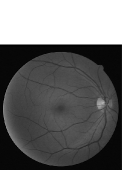

Refer to caption

Figure 4: Image segmentation. (a) The fundus image I𝐼I. (b) The green channel of the fundus image Igsubscript𝐼𝑔I_{g}. (c) The enhanced vessel image Imrsubscript𝐼𝑚𝑟I_{mr}. (d) The background regions B𝐵B. (e) The unknown regions U𝑈U. (f) The denoised preliminary vessel regions V2subscript𝑉2V_{2}

III-A1 Image Segmentation

The goal of image segmentation is to divide the input image into three regions: the vessel (foreground), background and unknown regions. Firstly the enhanced vessel image Imrsubscript𝐼𝑚𝑟I_{mr} is segmented into three regions: the background regions (B𝐵B), unknown regions (U𝑈U) and preliminary vessel regions (V1subscript𝑉1V_{1})

Imr={Bif 0<Imr<p1Uif p1Imr<p2V1if p2Imrsubscript𝐼𝑚𝑟cases𝐵if 0<Imr<p1𝑈if p1Imr<p2subscript𝑉1if p2ImrI_{mr}=\left\{\begin{array}[]{rl}B&\text{if $0<I_{mr}<p_{1}$}\\ U&\text{if $p_{1}\leqslant I_{mr}<p_{2}$}\\ V_{1}&\text{if $p_{2}\leqslant I_{mr}$}\end{array}\right. (7)

where p1=0.2subscript𝑝10.2p_{1}=0.2 and p2=0.35subscript𝑝20.35p_{2}=0.35 restrict the unknown region as thin as possible in order to achieve the better matting result [34, 28]. In order to remove the noise regions in V1subscript𝑉1V_{1}, the regions with Area>a1𝐴𝑟𝑒𝑎subscript𝑎1Area>a_{1} in V1subscript𝑉1V_{1} are extracted firstly (V1superscriptsubscript𝑉1V_{1}^{*}). Then regions in V1superscriptsubscript𝑉1V_{1}^{*} whose Extente1𝐸𝑥𝑡𝑒𝑛𝑡subscript𝑒1Extent\leq e_{1} && VRatior𝑉𝑅𝑎𝑡𝑖𝑜𝑟VRatio\leq r && Soliditys𝑆𝑜𝑙𝑖𝑑𝑖𝑡𝑦𝑠Solidity\geq s are abandoned, resulting in the denoised preliminary vessel regions V2subscript𝑉2V_{2}. An example of image segmentation is shown in Fig.4.